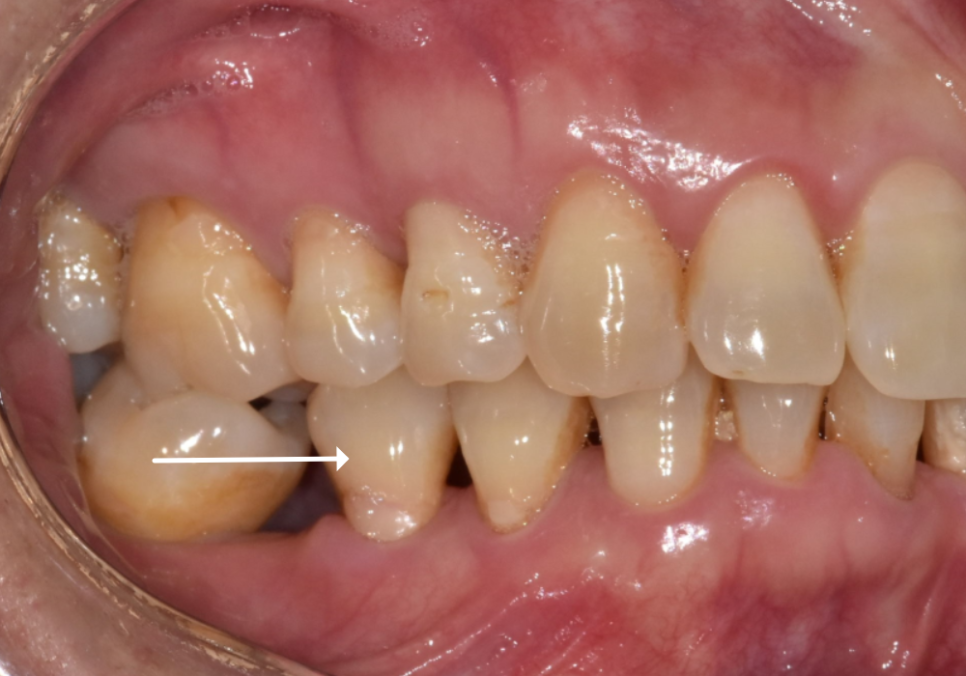

오른쪽 아래(#46)와 왼쪽 아래 맨 끝(#37)

치아를 발치한 지 꽤 오래된 상태였죠.

| 1) 오른쪽 어금니#47,48 어금니들이 빈 곳으로 많이 쏠려 #46 상실 부위에 임플란트를 심을 공간이 부족한 상태2) 왼쪽 어금니위쪽 어금니(#27)가 맞물릴 곳이 없어 아래로 정출되어 내려온 상태 |

보통 사랑니는 대부분 발치하는 경우가 많지만,

이 환자분은 상황이 달랐습니다.

어금니들이 앞으로 이동하면서

오히려 사랑니가 앞 어금니 역할을 대신하며

저작 기능을 하는 상태였는데요~